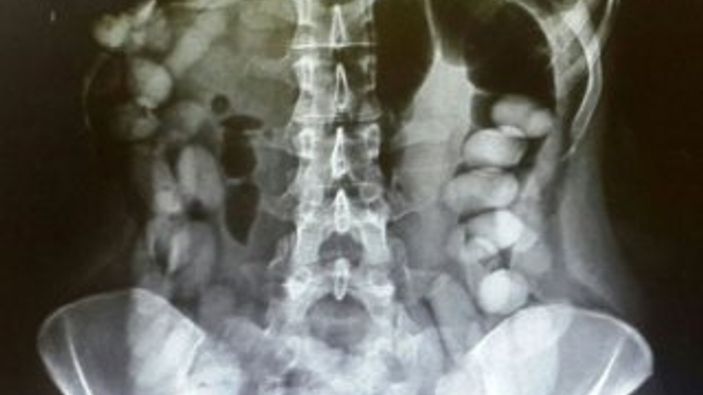

Tayland basınındaki haberlere göre, gümrük memurları x-ray cihazından geçen Suamu Nkele'nin midesinde bazı maddeler göründüğünü tespit etti.